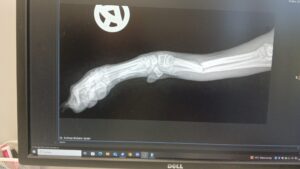

Lea braucht eure Unterstützung

Lea ist gerade einmal 4,5 Monate alt und hat sich ihr Vorderbein ganz unglücklich gebrochen.

Sie ist vom Schoss gesprungen und ganz ungünstig gefallen.

Wir hatten gehofft, ihr eine OP ersparen zu können – die Aussagen der Chirurgen ist aber ganz klar eine andere.

Eine OP ist die einzige Chance, dass Leas Beinchen wieder richtig zusammenwächst.